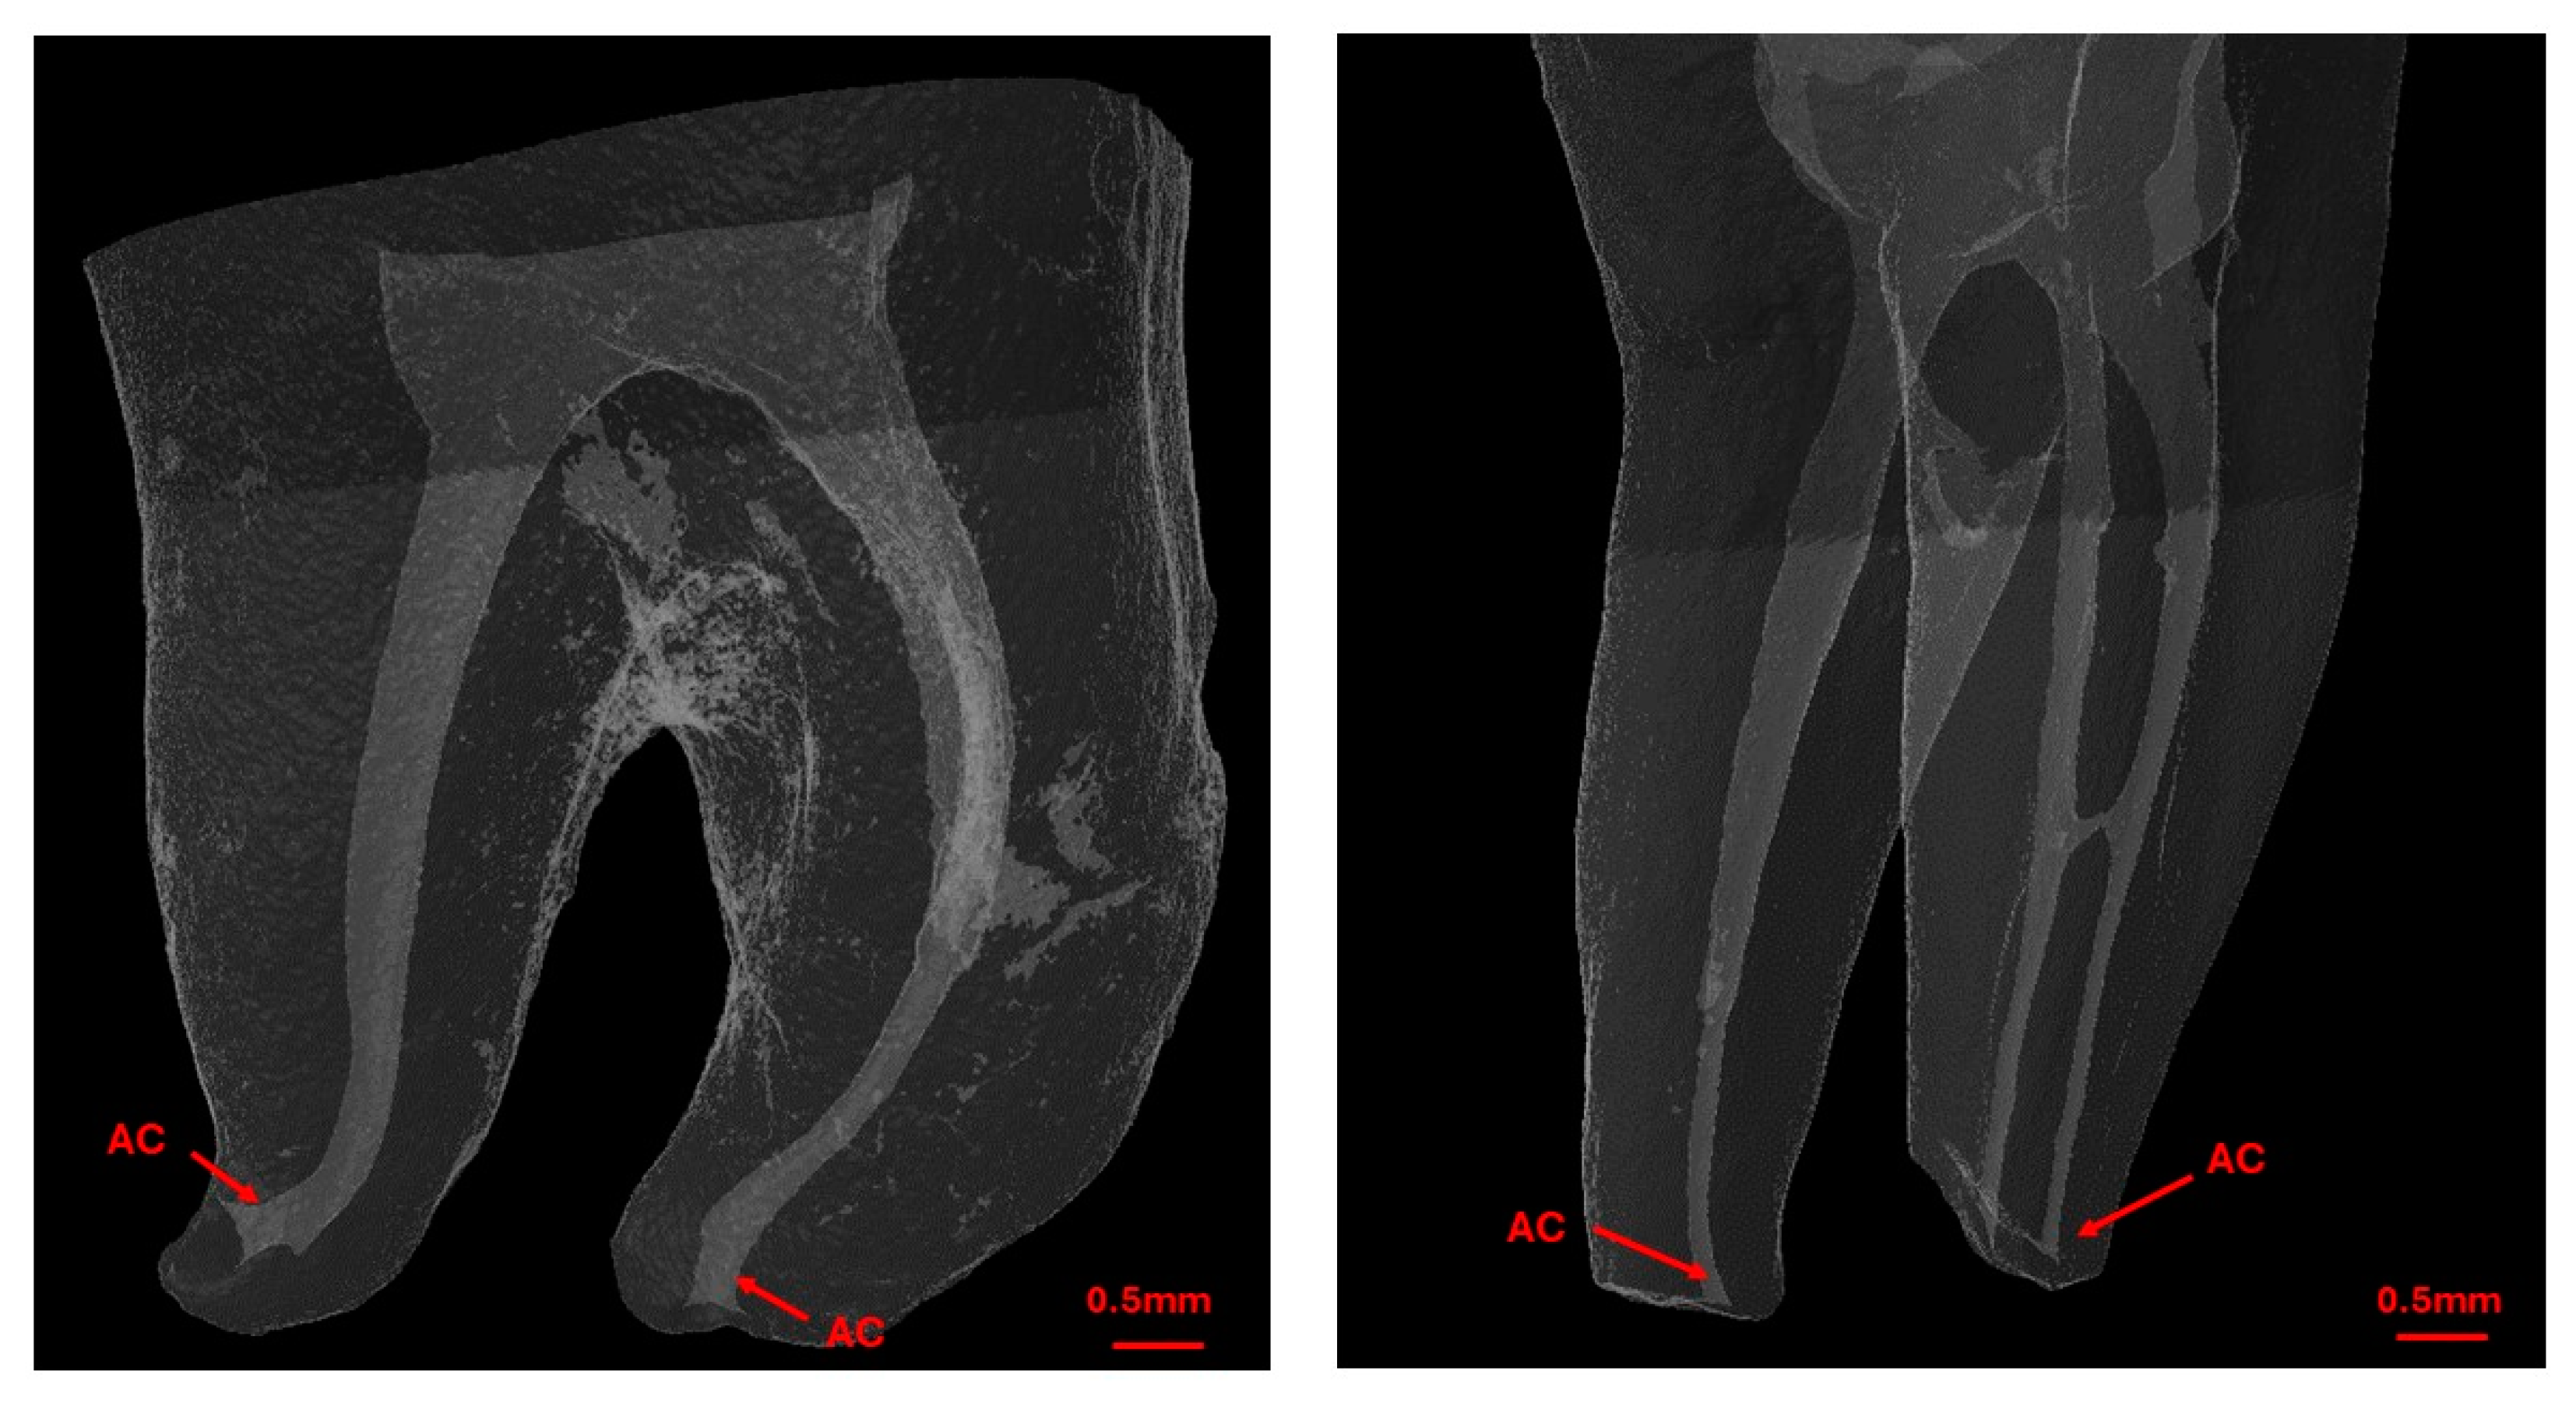

2.5. First Scan—Pre-WL Measurement

Prior to determining the WL of root canals, the first scan captured detailed anatomical data. A single operator identified the apical constriction (AC) as the most apical zone with the smallest cross-sectional area that extends at least 0.1 mm (Figure 3). The most apical position of the AC was marked and used as a reference point for the subsequent EAL measurements. During this scan, the distance between the AC and major foramen (AF) was recorded for each canal.

Figure 3. Micro-CT reconstructions of the tooth showing the external and internal anatomy of the root canal system with AC highlighting the position of the apical constriction.